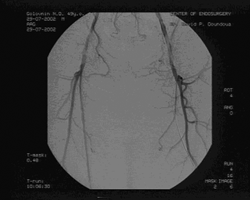

Пациент обратился вновь в клинику через 1,5 года после первичной ангиопластики и через год после повторной с перемежающейся хромотой слева через 400м, правая нк не беспокоила. Пациент также обратил внимание на умеренный отек левой стопы. ЛПИ слева составил 0,64. Вновь проведена ангиография, на этот раз трансрадиальным доступом, выявлены рестенозы внутри стентов в устье левой ПБА, рестеноз в средней порции левой ПБА, где стентирование не проводилось, рестеноз внутри проксимального стента в Гунтеровом канале. Правая нижняя конечность оставалась без гемодинамически значимых изменений. Обнаружен артериовенозный сброс в левой нижней конечности из подколенной артерии в одноименную вену. (см. рис. 4а и 4б)

| Рис. 4а Контрольная ангиография через 18 мес. Радиальный доступ. | Рис. 4б Дооперационная ангиография через 18 месяцев с артерио-венозным сбросом. Доступ через подколенную артерию |

Доступом в подколенной области выделена подколенная артерия слева, перевязано артериовенозное соустье, пунктирована подколенная артерия и произведена баллонная ангиопластика стенозов левой ПБА с хорошим непосредственным результатом, не потребовавшая дополнительного стентирования. (см. рис. 5)

Рис. 5. Контрольная ангиография после ЧТА левой ПБА.